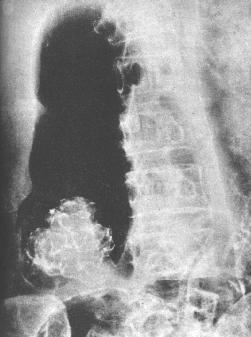

| 浸润型结肠癌。降结肠下段局限性环状狭窄,与正常肠管分界截然,肿块远端有环状粘膜纹套入。

钡灌肠所见: 1.增生型:自肠壁向腔内生长,如菜花状或息肉状充盈缺损,外缘不规整,境界清楚,局部粘膜皱襞破坏消失。若肿块较大,钡剂通过受阻,充盈缺损部位可扪及肿块。 2.浸润型:多呈向心性环形狭窄僵硬,边缘光滑,病变区与正常肠管分界清楚,粘膜皱襞破坏消失,结肠袋消失,常伴有梗阻。 3.溃疡型:肿瘤生长如扁平蝶状,大部分突入肠腔,主要表现为腔内不规则龛影,在肠壁一侧可出现半月征,龛影周围有宽狭不一的环堤,有指压迹。 |